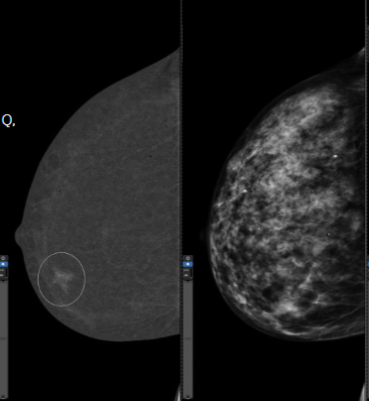

Contrast-enhanced diagnostic mammogram image

Left: Recombined image of the CEM exam showing iodine uptake.

Right: Standard digital mammogram